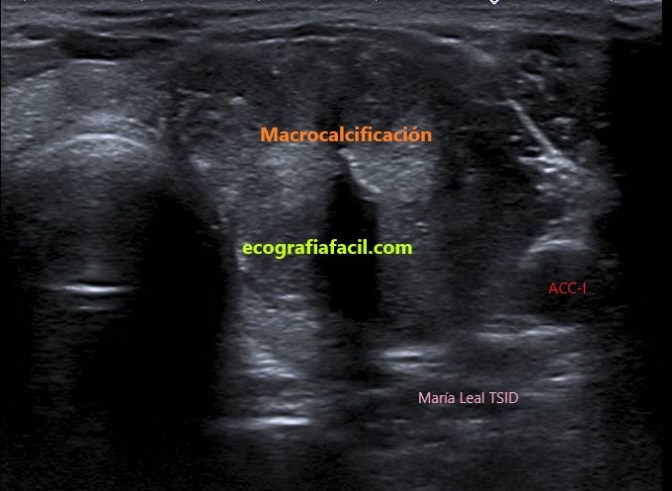

5. POR LOS FOCOS ECOGÉNICOS:

MACROCALCIFICACIONES: